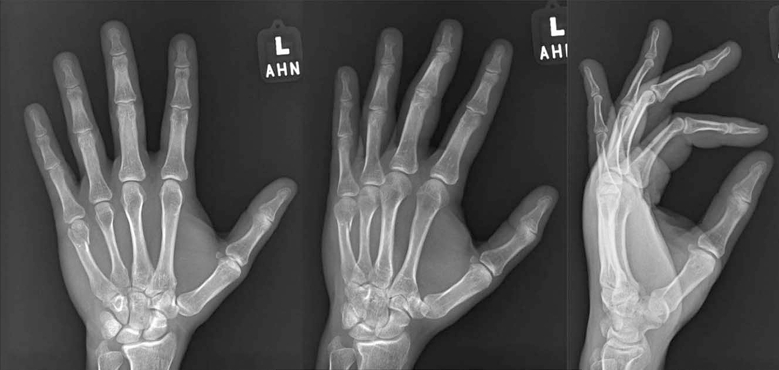

3. Percutaneous K-Wire Fixation for Metacarpal Neck Fractures

4. Percutaneous K-Wire Fixation for Adjacent Metacarpal Neck and Base Fractures